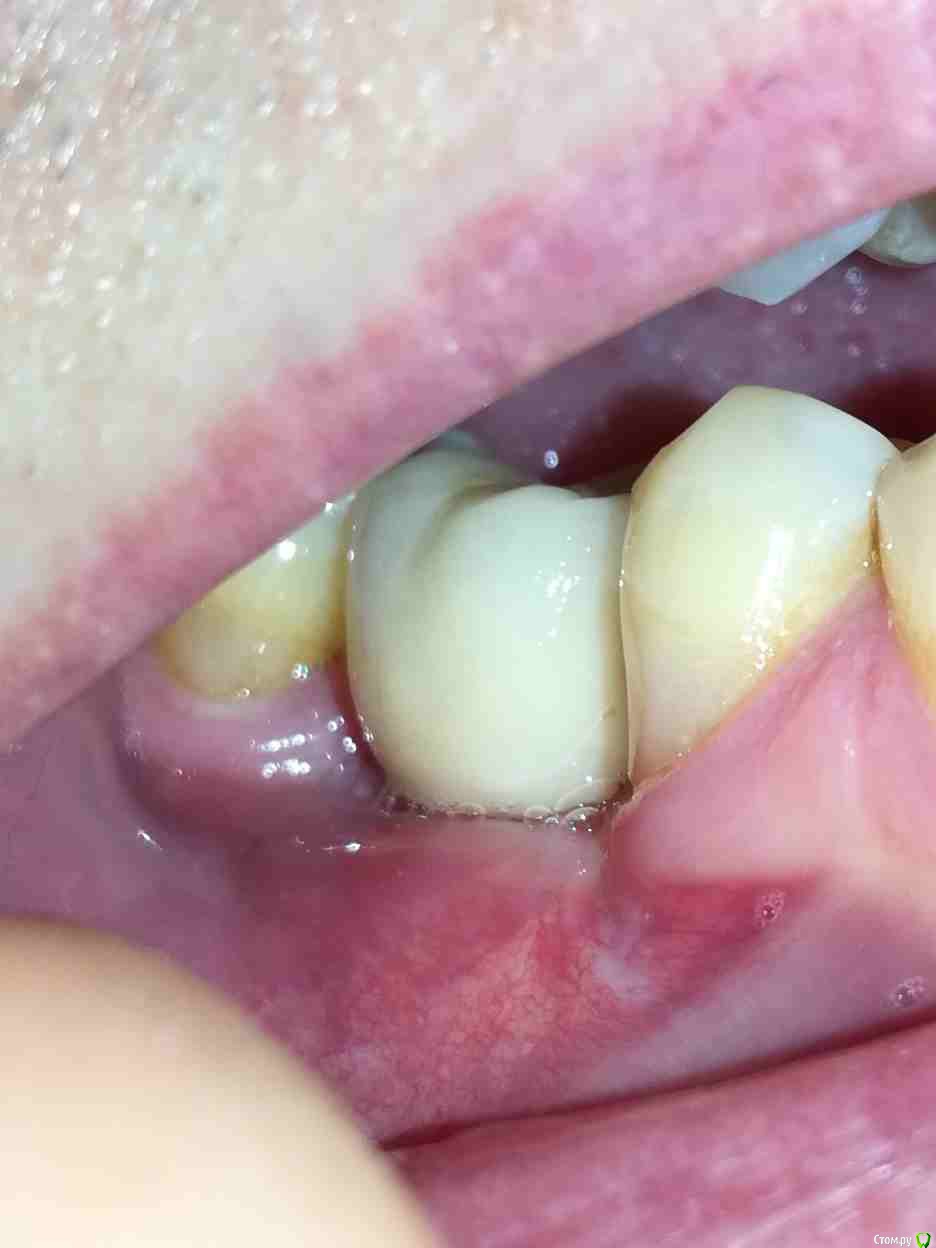

Alex19_73 Опубликовано 15 февраля, 2017 Поделиться Опубликовано 15 февраля, 2017 Доброго времени суток!Оцените пожалуйста качество имплантации и последующего протезирования. Имплантация проводилась с расщеплением гребня, имплант оказался смещен внутрь относительно других зубов. Хотел металлокерамическую коронку на винте, но ортопед сказал что возможно поставить только на цементе т.к. имплант сильно смещён внутрь. Вчера установили коронку но после дома стал разглядывать и она мне совсем не понравилась. По ощущениям очень неприятна, громоздка, когда жуешь то же как то не как родной зуб, языки щека постоянно по ней трут. С обратной стороны коронки обнаружил что то белое, наверно цемент, зубочисткой и ирригатором снять не удалось. Ортопед обратную поверхность зуба ковырял крюком счищая цемент. Это белое спускается с коронки прямо на десну.Можно ли если это цемент счистить его не испортив керамику коронки? Не может ли спровоцировать переимплантит такое затекание цемента, и вообще насколько это профессионально и соответствует протоколам (работа имплантолога и ортопеда)? Заранее спасибо. Ссылка на комментарий

Alex19_73 Опубликовано 16 февраля, 2017 Автор Поделиться Опубликовано 16 февраля, 2017 Как оказалось позже, во время еды, под зуб ещё и большие куски еды попадают и там остаются, флос под зубом проходит очень свободно. Ссылка на комментарий